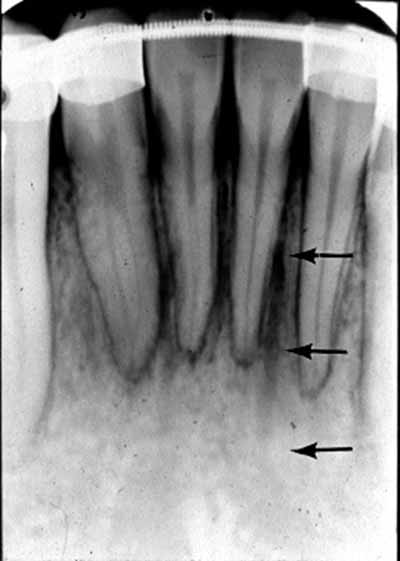

下顎の舌側表面の中央には骨の突起であるオトガイ棘があり、この骨の突起は口底の筋肉の付着部として機能します。オトガイ棘は、下顎の中切歯の下にある丸いまたはリング状のエックス線不透過構造として、X線写真上に描かれます。オトガイ棘と同じ領域の中央には舌孔があり、1つまたは複数の小さな丸いエックス線透過性の点として描かれています (画像17aおよび17bを参照)。

下顎の外側部に向かって後方に移動すると、犬歯、小臼歯、大臼歯が見えます。小臼歯と大臼歯の下には下顎管があり、薄いエックス線不透過性の境界に囲まれた幅広いエックス線透過性の線として現れます。下顎管は下顎の頬側表面にあるオトガイ孔に開口しています。口腔内画像では、オトガイ孔は小臼歯の根尖のすぐ下またはその高さにある丸いエックス線透過性の構造として確認できます(画像 18 および 19 を参照) 。下顎管は下顎枝にあるオトガイ孔から下顎孔まで下顎の外側部分全体に沿って走っています。多くの場合、臼歯の根尖のすぐ下か、同じ高さに位置します。等角投影と軸測投影の両方で、臼歯の頂点に重なって描かれることもあります(画像20と21を参照)。

オトガイ孔の画像では、下顎骨の基底部が見えることも珍しくありません。これは下顎の下縁を形成する、強いエックス線不透過性の線として現れます (画像20と21を比較)。